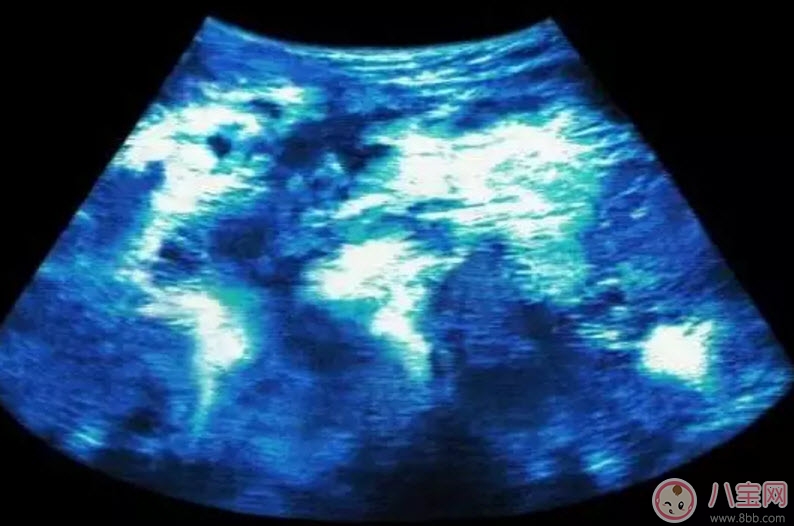

1、胎兒B超

這是檢查胎兒畸形的常用方法,一般在懷孕20~24周進(jìn)行。通過胎兒B超,可以看出胎兒的各個(gè)臟器,如果B超發(fā)現(xiàn)此時(shí)胎兒嚴(yán)重畸形,就應(yīng)及時(shí)流產(chǎn),以免拖至妊娠晚期給孕婦造成更大的痛苦。

不過,并不是所有的畸形胎兒都能用B超測出,因染色體異常而導(dǎo)致的先天愚型兒或一些微小畸形,B超就測不出來。另外,還有一些畸形要到孕晚期才能夠表現(xiàn)出來,所以這個(gè)時(shí)候的B超檢測也查不出胎兒畸形。而且,因?yàn)槌姆直媛视邢抟约凹夹g(shù)的原因,有些畸形會在超生檢查時(shí)漏診。

24周左右做三維彩超,可清晰顯示胎兒各部位臟器,了解胎兒生長發(fā)育情況,觀察頭,肢體及各臟器大體結(jié)構(gòu)是否有畸形。另外還要定期檢查胎心、血壓等等。